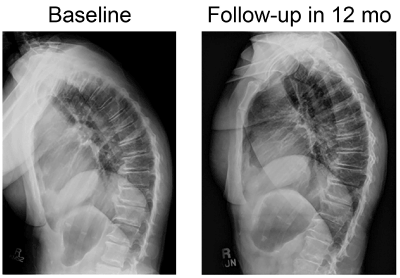

Patients’ neurologic evaluations showed no relevant deficits. Initially all patients had thoracic hyper kyphosis (kyphosis > 40°). On radiographic follow up the kyphosis angle had decreased more than 5 degrees (Figure 4). Table 1 shows patient gender, age, diagnoses, and pain level at baseline (0 [no pain] to 10 [maximum, unbearable pain]). Initial pain ranged from 4 to 10 on the pain scale (average: 7.8, SD: 1.7); on follow-up, pain ranged from 0 to 4 (average:1.0, SD: 2.3), resulting in a mean change of 6.8 (p < 0.0001) complete pain relief was achieved in all but 6 of the 27 patients. Their symptoms, which initially varied from severe headache, neck and upper back pain and sometimes also nagging flank pain had subsided or reduced substantially. All reported reduction in use of analgesics and no further complaint of headaches. During the trial the patients were able to decrease forward position of the head, neck and thoracic kyphosis while wearing the weight. (Figure 3,4).

Figure 4. Radiographs show reduction of kyphosis from baseline to 12-month follow-up.